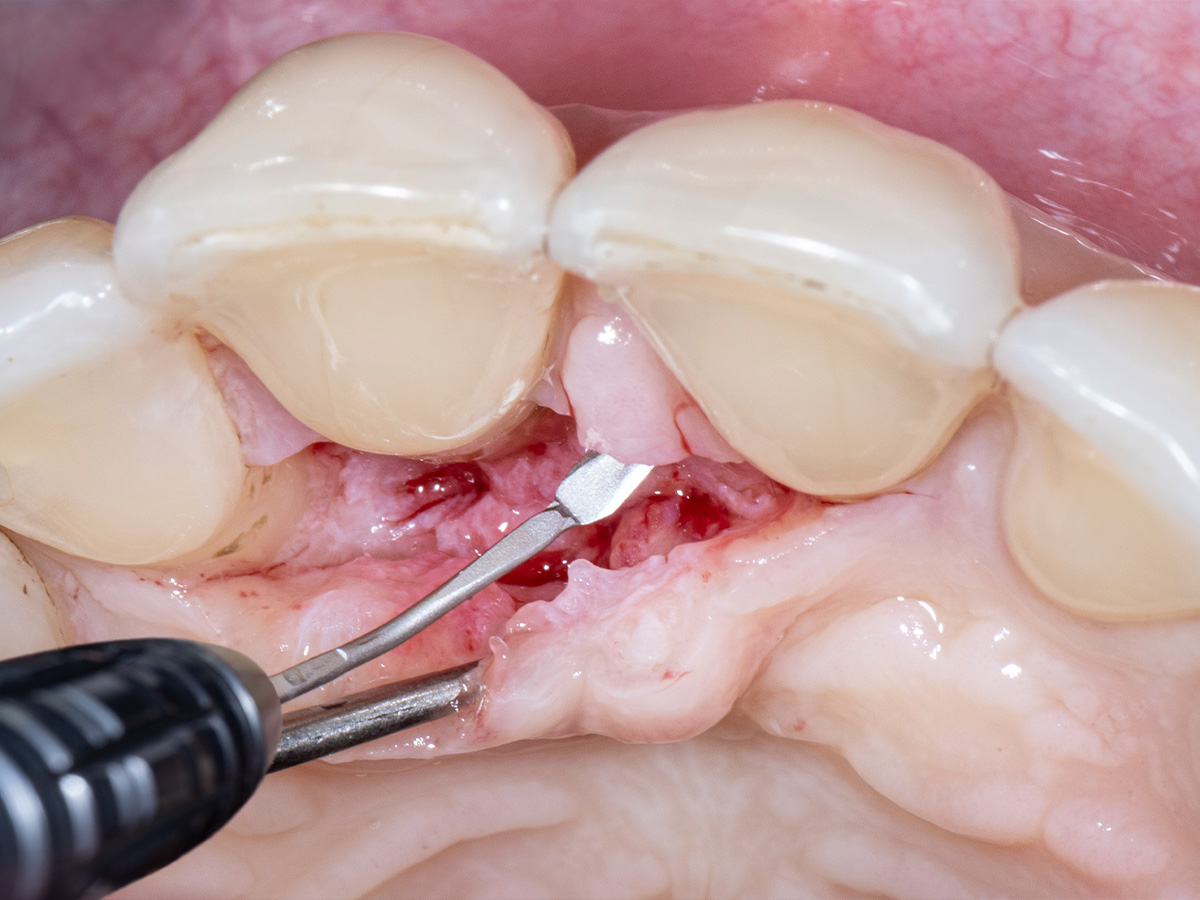

Während der intraoralen Untersuchung wurden eine erhöhte Beweglichkeit sowie erhöhte Taschensondierungstiefen und klinische Entzündungszeichen an Zahn 11 festgestellt. Ein intraorales Röntgenbild wurde angefertigt. Die intraossäre Defektkomponente gemeinsam mit dem hohen Niveau an Mundhygiene bieten eine gute Grundlage für einen regenerativ-parodontalchirurgischen Eingriff. Zehn Tage vor dem Eingriff wurde der Zahn mit dem Nachbarzahn verblockt und ein lokales Antibiotikum in die parodontale Tasche appliziert, um zum Zeitpunkt des Eingriffs möglichst entzündungsarme Verhältnisse vorzufinden. Unmittelbar vor Beginn des chirurgischen Eingriffs wurde der Defektboden mit einer Parodontalsonde ausgelotet, um Informationen über die dreidimensionale Defektmorphologie zu erhalten (Abb. 1-3).

Aufgrund der hohen Lachlinie haben wir uns für eine horizontale Inzision durch die Papillenbasis auf der palatinalen Seite sowie intrasulkuläre Inzisionen um die Nachbarzähne entschieden. Auf diese Weise können Oberflächeninzisionen auf der bukkalen Seite, die zu sichtbarem Narbengewebe führen können, vermieden werden.

Um den mesiobukkalen Aspekt des Defekts zu erreichen, wurde ein zweiter Lappen mit einer ultradünnen und biegbaren Keydent Spin Blade 360 präpariert, die an die jeweilige anatomische Situation angepasst werden kann und präzise intrasulkuläre Inzisionen im Interproximalraum sowie ein vorsichtiges Abtrennen des entzündlichen Infiltrats vom Weichgewebe und ein anschließendes sanftes Herauslösen auf die bukkale Seite ermöglicht.